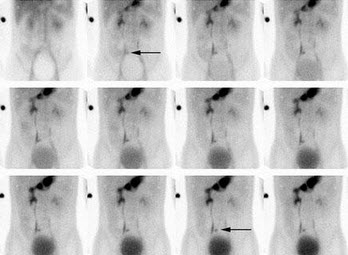

8、多项选择题

女,35岁,发现颈部包块就诊,行TcO甲状腺显像如图,可能的诊断为()

A.Plummer病

B.此结节为“热结节”

C.甲状腺功能亢进

D.桥本氏病

E.甲状腺癌

点击查看答案